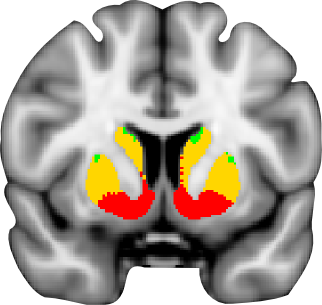

Oxford-GSK-Imanova structural and connectivity striatal atlases

Connectivity atlas

A probabilistic atlas of sub-striatal regions, segmented according to their white-matter connectivity to cortical areas. This connectivity atlas reports anatomical connection from points in the striatum to each of 7 cortical zones obtained using probabilistic diffusion tractography in multiple subjects. For more details see the Striatal Connectivity Atlas web page.

Structural atlas

Atlas of sub-striatal regions, segmented according to the anatomical structure. Striatum is divided into caudate, putamen and ventral striatum according to the guidelines described by Tziortzi et al (2011). The sub-regions were manually delineated on the non-linear MNI152 template. For more details see the Structural Striatal Atlas web page.